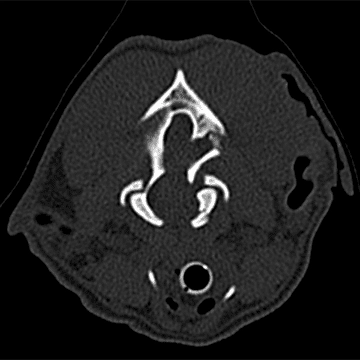

CT showed closed complete comminuted (more than two pieces) variably displaced traumatic fractures of the left petrous temporal bone, left occipital bone, and occipital condyle with secondary subluxation (partial dislocation), extra axial compression of the medulla oblongata and cerebellum, left tympanic cavity effusion (likely hemorrhagic), and superficial subcutaneous edema and/or hemorrhage.

In summary, MRI and CT revealed a fracture of the occipital bone at the back of the skull, which was compressing the cerebellum and brainstem, and also a fracture of the occipital condyle, where the skull connects to the first vertebra (AO luxation).